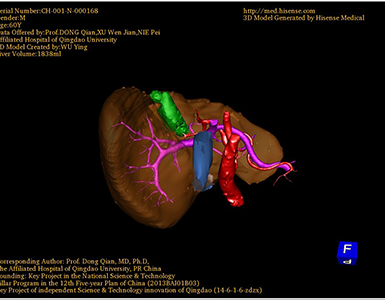

将0.625mm双源薄层CT资料的静脉期和动脉期Dicom格式文件导入海信CAS系统。

通过调节窗宽窗位调整CT序号,对肿瘤,肝实质,胆囊,下腔静脉,肿瘤,肝动脉、门静脉及肝静脉等进行三维重建;系统自动计算肿瘤体积和肝脏体积。

术前手术方案的规划。

术前三维重建:

重建图片